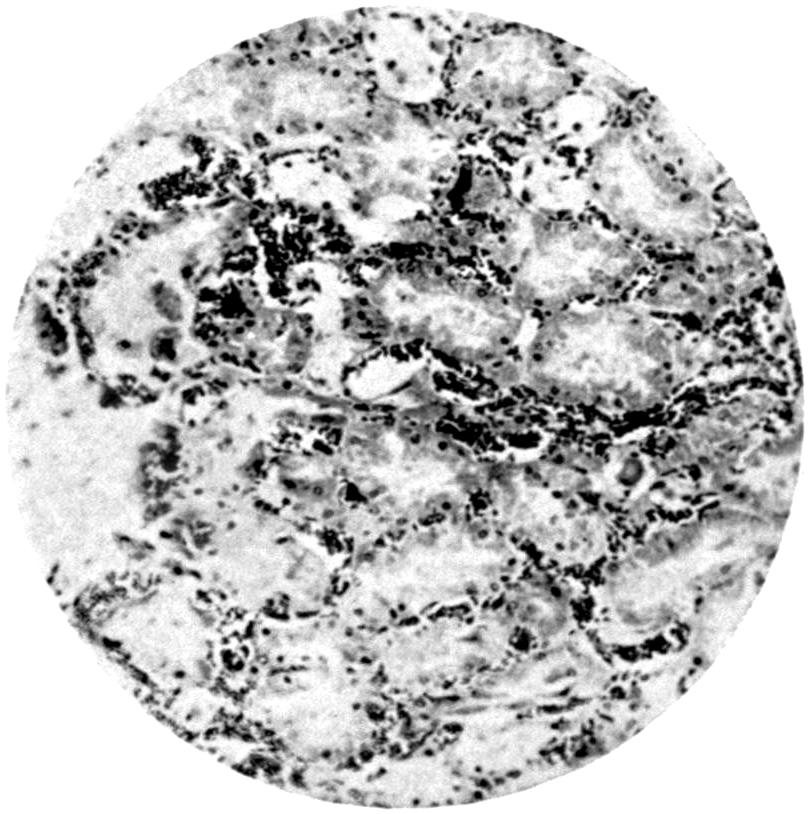

LIST OF PLATES

FACING

PAGE

Plate III. 95